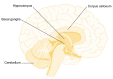

Children prenatally exposed to alcohol can suffer from serious cognitive deficits and behavioral problems as well as from alcohol-related changes in brain structure. Neuropsychological studies have identified deficits in learning and memory as well as in executive functioning both in children with fetal alcohol syndrome and in children with less severe impairments. Both groups of children also exhibit problem behaviors, such as alcohol and drug use, hyperactivity, impulsivity, and poor socialization and communication skills. Brain imaging studies have identified structural changes in various brain regions of these children--including the basal ganglia, corpus callosum, cerebellum, and hippocampus--that may account for the cognitive deficits. Functional brain imaging studies also have detected changes in alcohol-exposed children indicative of deficits in information processing and memory tasks.